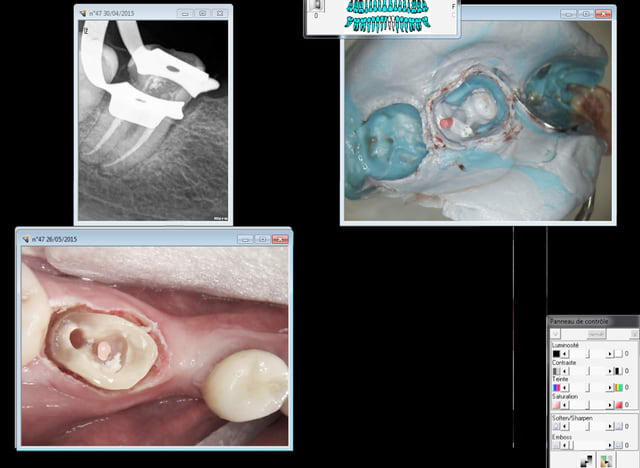

Tu fais comment avec ta caméra dans un cas comme ca ? -))))

Capture d e cran 2015 06 04 17.16 - Eugenol

Capture d e cran 2015 06 04 17.15 - Eugenol

> Tu fais comment avec ta caméra dans un cas comme ca ? -))))

Forcément empreinte physique.